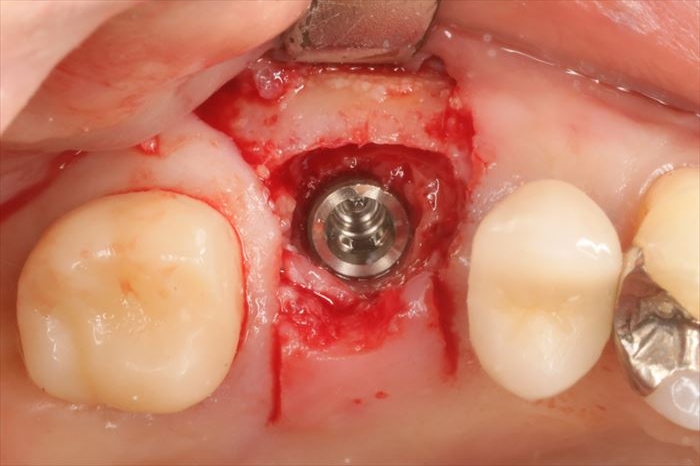

粘膜を剥離して骨の状態を確認します。

CTデータ通り、すり鉢状に骨吸収が起こっています。

ここから適切な位置にドリリングしなおします。

ストローマンインプラント BLT φ4.8mm 長さ8mmを埋入します。

_

埋入角度も理想的になるように埋入します。